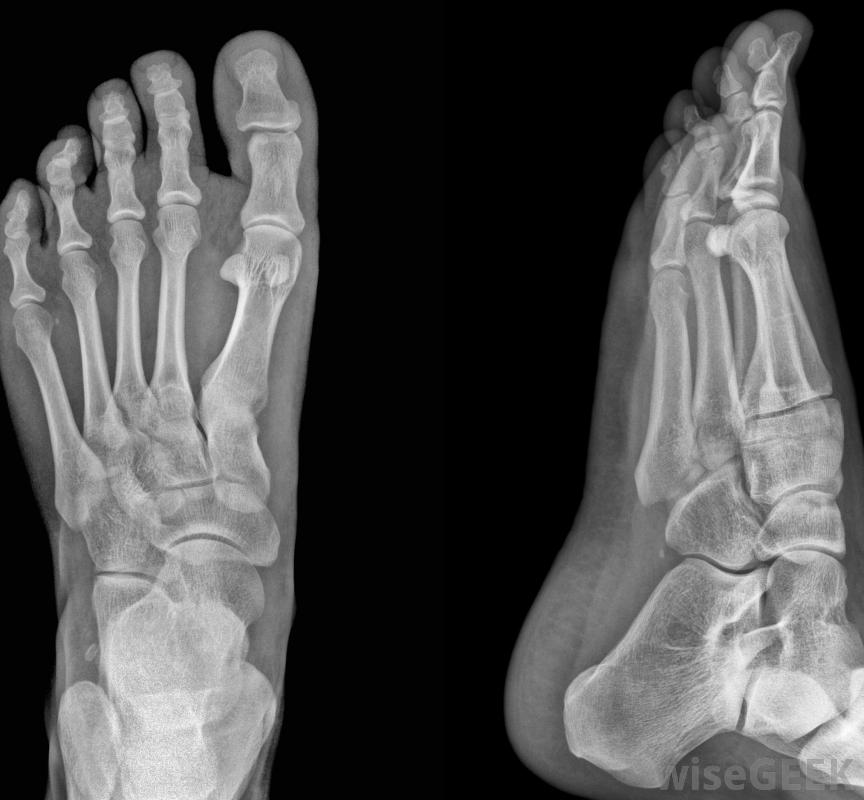

根据患者的特殊情况,可以使用x光片检查囊肿,外科医生可能会发现有必要切除从脚部侧面凸出的骨块。这种手术被称为束膜切除术,它可以去除隆起部分,但不能固定患者的大脚趾的位置。有时,外科医生会从患者的大脚趾上取下整块骨头。这种手术被称为截骨术,用于矫正患者的大脚趾或大脚。在这种情况下,外科医生可能会使用特殊的装置,比如螺丝钉或金属丝,为了在愈合过程中保持骨骼的稳定。

取决于手术类型,手术后的恢复可以持续几个月。在某些情况下,在bunion手术中,可能需要移除患者第一个跖骨末端的骨头。跖骨是足部的长骨之一。第一个跖骨与跖趾关节相连,跖趾关节是人的大脚趾底部的关节。在取出所需数量的骨后,外科医生随后会重塑受影响的骨骼,包括大脚趾骨。